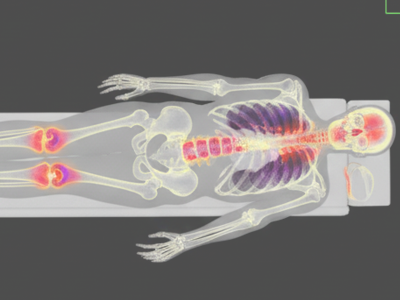

Our Imaging Services

Merivale Medical Imaging offers a full range of outpatient diagnostic imaging services across Ottawa, Kanata, and the Ottawa Valley, from MRI and CT to ultrasound, X-ray, and nuclear medicine.